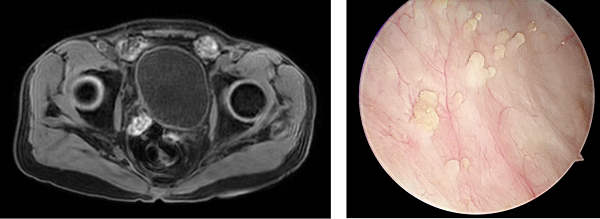

1.手术“亮剑”。泌尿外科团队率先出击,为张先生实施了“经尿道膀胱肿瘤最大化电切术”,切除了肉眼可见的肿瘤组织。术后病理确诊为高级别浸润性尿路上皮癌,这颗“毒瘤炸弹”的威力果然不容小觑。

术后影像显示肿瘤被切除